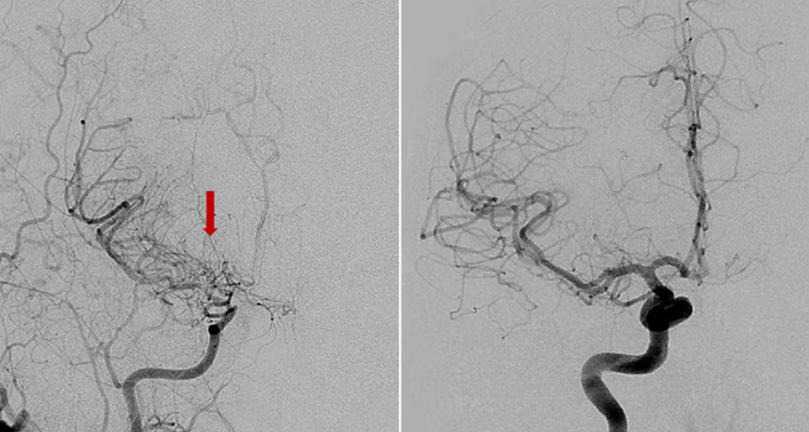

Moyamoya disease is a rare cerebrovascular disease characterized by the slow narrowing of major brain blood vessels over time, resulting in reduced blood flow to specific parts of the brain. With time, these changes may become severe and lead to ischemic stroke, hemorrhagic stroke, and seizures. The Japanese doctors who discovered it named the condition moyamoya, which means “puff of smoke,” Read more…